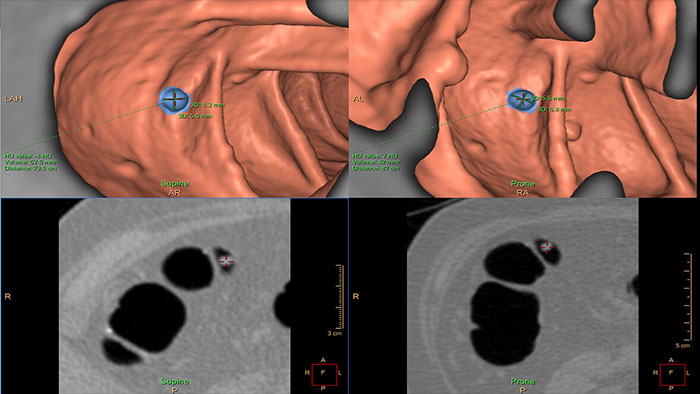

Assessing lung nodules over time

Enables review and analysis of thoracic CT images, providing segmentation, quantification and characterization of physician-indicated lung nodules. The application can be used in both diagnostic and screening evaluations, supporting Low Dose CT Lung Cancer Screening*

Automatically detect potential polyps in CT colonography exams

VC VeraLook CAD* uses image processing and pattern recognition technology identify colon polyps in CT colonography images, which can help streamline the reading process and improve workflow for radiologists while supporting accuracy, consistency and productivity in colon cancer screenings. Indicated for use as a second read, VeraLook is designed to enhance clinician accuracy and efficiency.

Reducing reading times in virtual colonoscopy

Enables 3D visualization of colon scans. The application automatically segments the air-filled colon and displays a calculated navigation path. The Perspective Filet view provides a synchronized display of the full colon surface wall with a single unidirectional view, reducing the need to review in both directions.